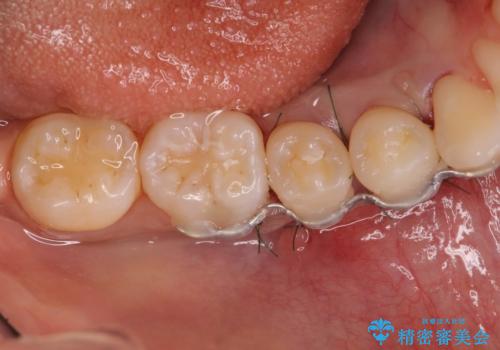

患者様は、他院で右下の歯を抜歯かもと言われました。全体の歯周病はなく、右下の1歯だけ骨が極端に減少していました(初診時歯周ポケット7mm。通常は3mm以下。)。その歯だけ咬合が強いことが原因と考えられたため、咬合を弱くする処置と減少した骨を再生する処置が必要になりました。

骨の再生治療手術をして10か月経過観察をしたのち、骨を平坦化する手術を行い、治療終了となりました。

・手術後はしばらくワイヤー等で固定する必要があります。